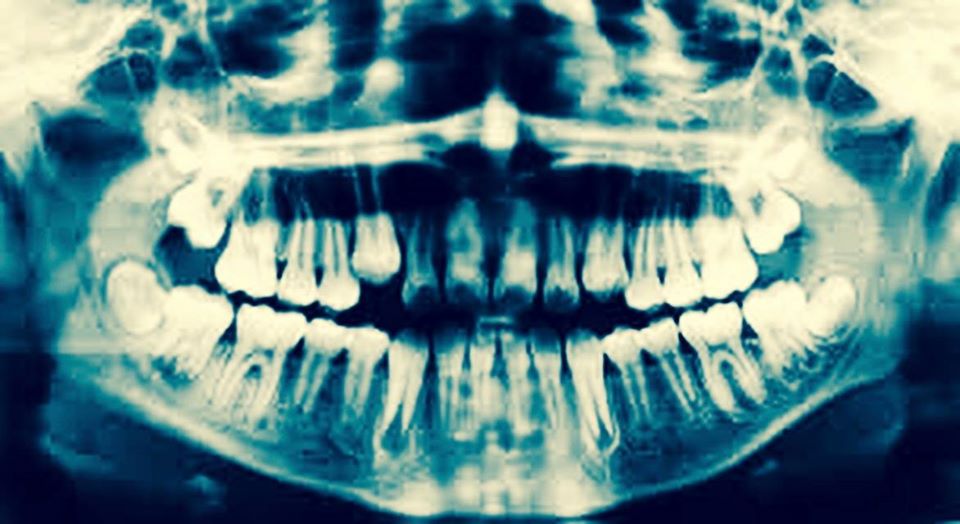

Es más, ¿Alguna vez un médico con la visión convencional ha relacionado un cuadro de tendinitis del codo (epicondilitis) con el antecedente de una endodoncia previa al inicio del cuadro?, o ¿un cuadro de dolor de rodillas (gonalgia) con la fractura o extracción de algún incisivo?, o más aún, ¿una enfermedad autoinmune con unas muelas del juicio impactadas? Más bien parece raro relacionar este tipo de problemas con antecedentes odontológicos.

Con todo, desde la visión de la Terapia Neural, la salud dental puede estar íntimamente relacionada con la génesis de algún problema de nuestro organismo, y ello ocurre porque nuestros dientes están interrelacionados gracias a la gran red interconectada que forma el Sistema Nervioso Neurovegetativo, encargado de comunicar todas las partes de nuestro organismo para que pueda funcionar armónicamente.

Siguiendo esta técnica, alteraciones funcionales en el sistema digestivo, tales como colon Irritable, estreñimiento, gastritis, problemas respiratorios como obstrucciones bronquiales, enfermedades crónicas respiratorias, problemas del aparato urogenital (cistitis a repetición), dolores articulares a nivel cervical, lumbar, hombros, codos, muñeca, manos, cadera, rodilla tobillos, pies, y un largo etcétera, pueden verse beneficiados si consideramos a los dientes como un antecedentes importante en la génesis del problema..